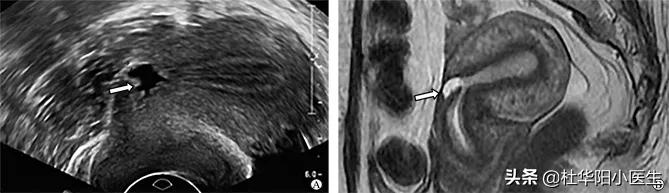

三角形憩室(无回声尖端指向子宫浆膜层,底部朝向宫腔,并与宫腔相通)

A示超声下三角形憩室图 ;B示同一患者磁共振下三角形憩室(箭头示子宫瘢痕憩室)

图片来自:文献:阴道超声和磁共振在剖宫产术后子宫瘢痕憩室中的联合应用价值